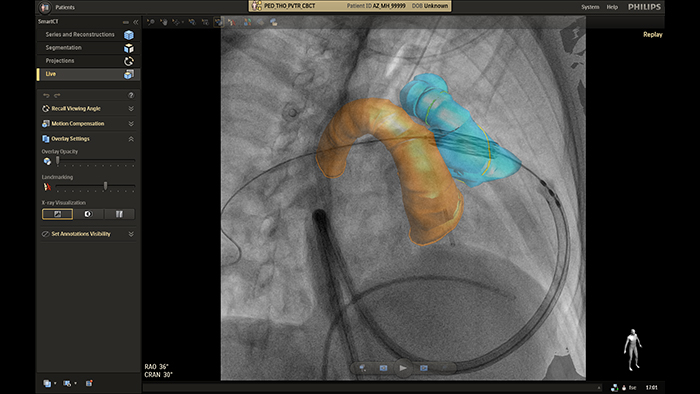

SmartCT live guidance

The Philips image-guided therapy clinical application software SmartCT allows any clinical user to perform 3D imaging regardless of their level of experience with 3D imaging*. Via the touch screen at the table, you can access clinically tailored 3D acquisition protocols and advanced visualization and measurement tools that depict the type and extent of disease with great detail. *The user level of expertise required is described in the Instructions for Use as the Intended Operator Profile.